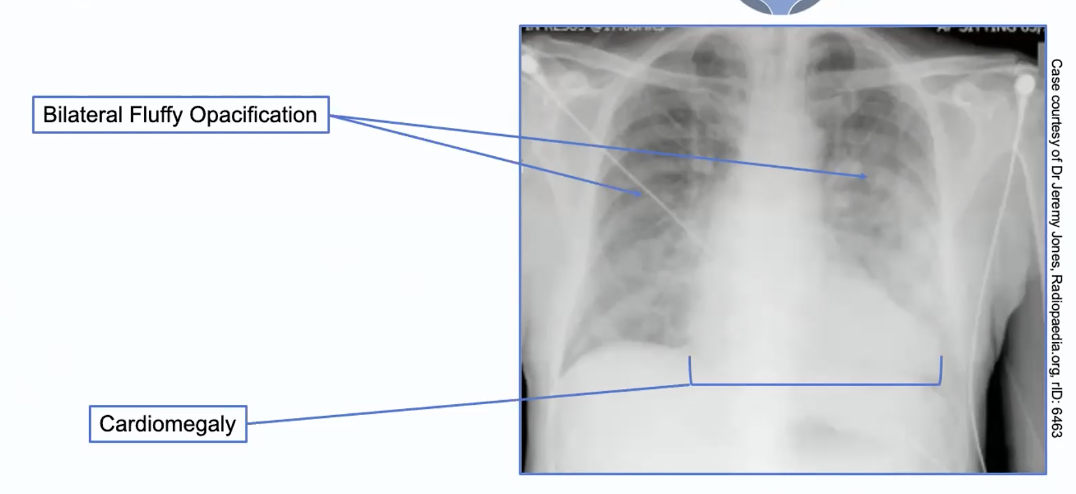

CXR for HF

Bilateral opacification

Cardiomegaly